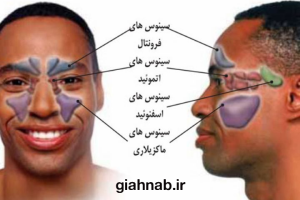

سینوزیت یکی از بیماریهای شایع تنفسی است که به دلیل التهاب و عفونت در سینوسهای اطراف بینی

ایجاد میشود. این بیماری میتواند زندگی روزمره فرد را مختل کرده و باعث سردردهای مزمن، گرفتگی بینی وخستگی شود. در این مقاله به بررسی جامع این بیماری از دیدگاه طب مدرن و سنتی، روشهای درمانی،

سینوزیت (Sinusitis) به التهاب یا عفونت سینوسهای پارانازال اطلاق میشود که معمولاً ناشی از عفونت